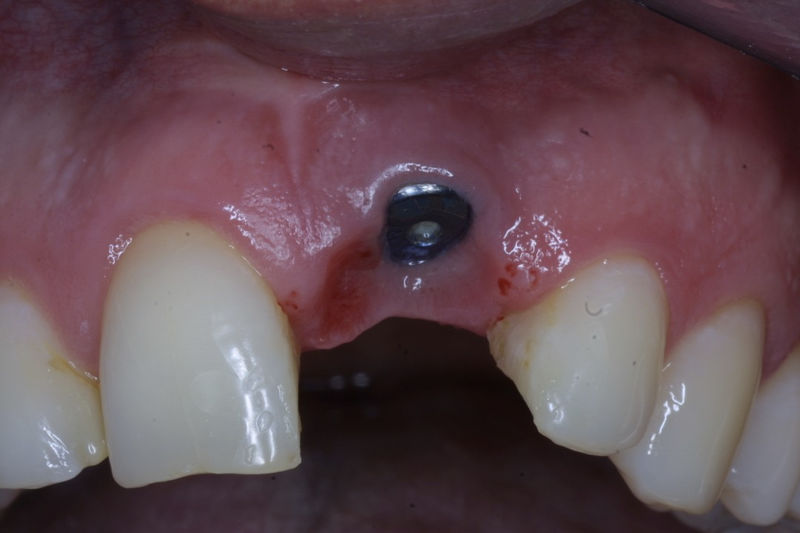

Implante fracasado, extracción, carillas, coronas y prótesis fija.